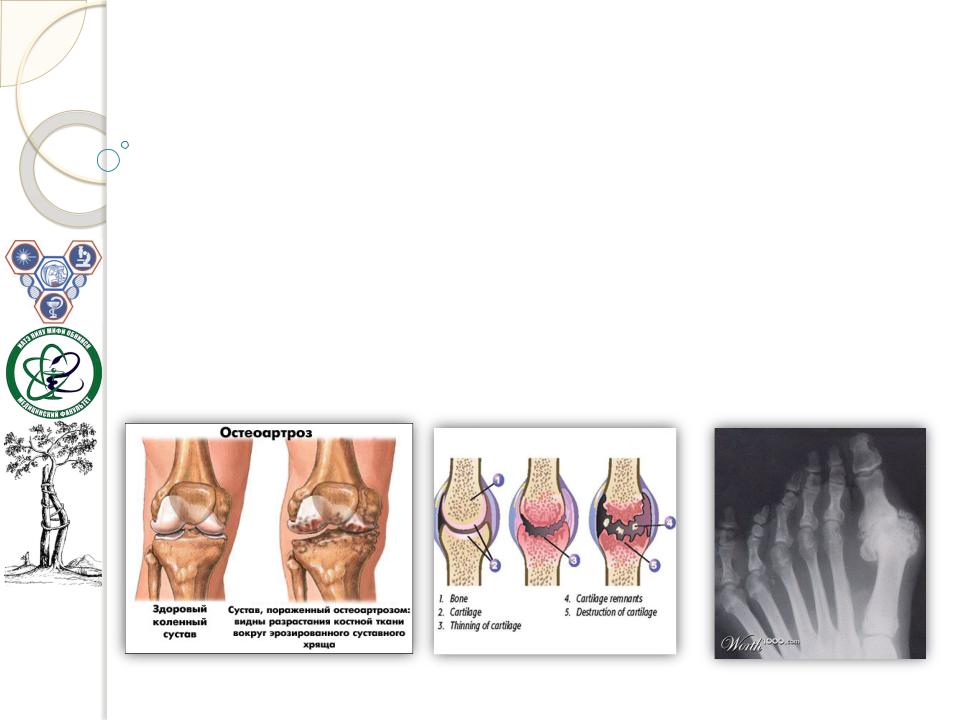

Деформирующийостеоартроз— этодегенеративно-дистрофическое заболевание суставовспервичнойдегенерациейсуставногохряща,с последующимиизменениямисуставнойповерхностииразвитиемкраевых остеофитов,чтоведёткдеформациисуставов.

Восновеостеартрозалежатколичественныеикачественныеизменения протеогликанов (основногодействующеговеществахряща)иповреждение хондроцитов.Протеогликаныобладают антигенными свойствами, следовательно, могутслужитьисточникомаутоиммунных реакций